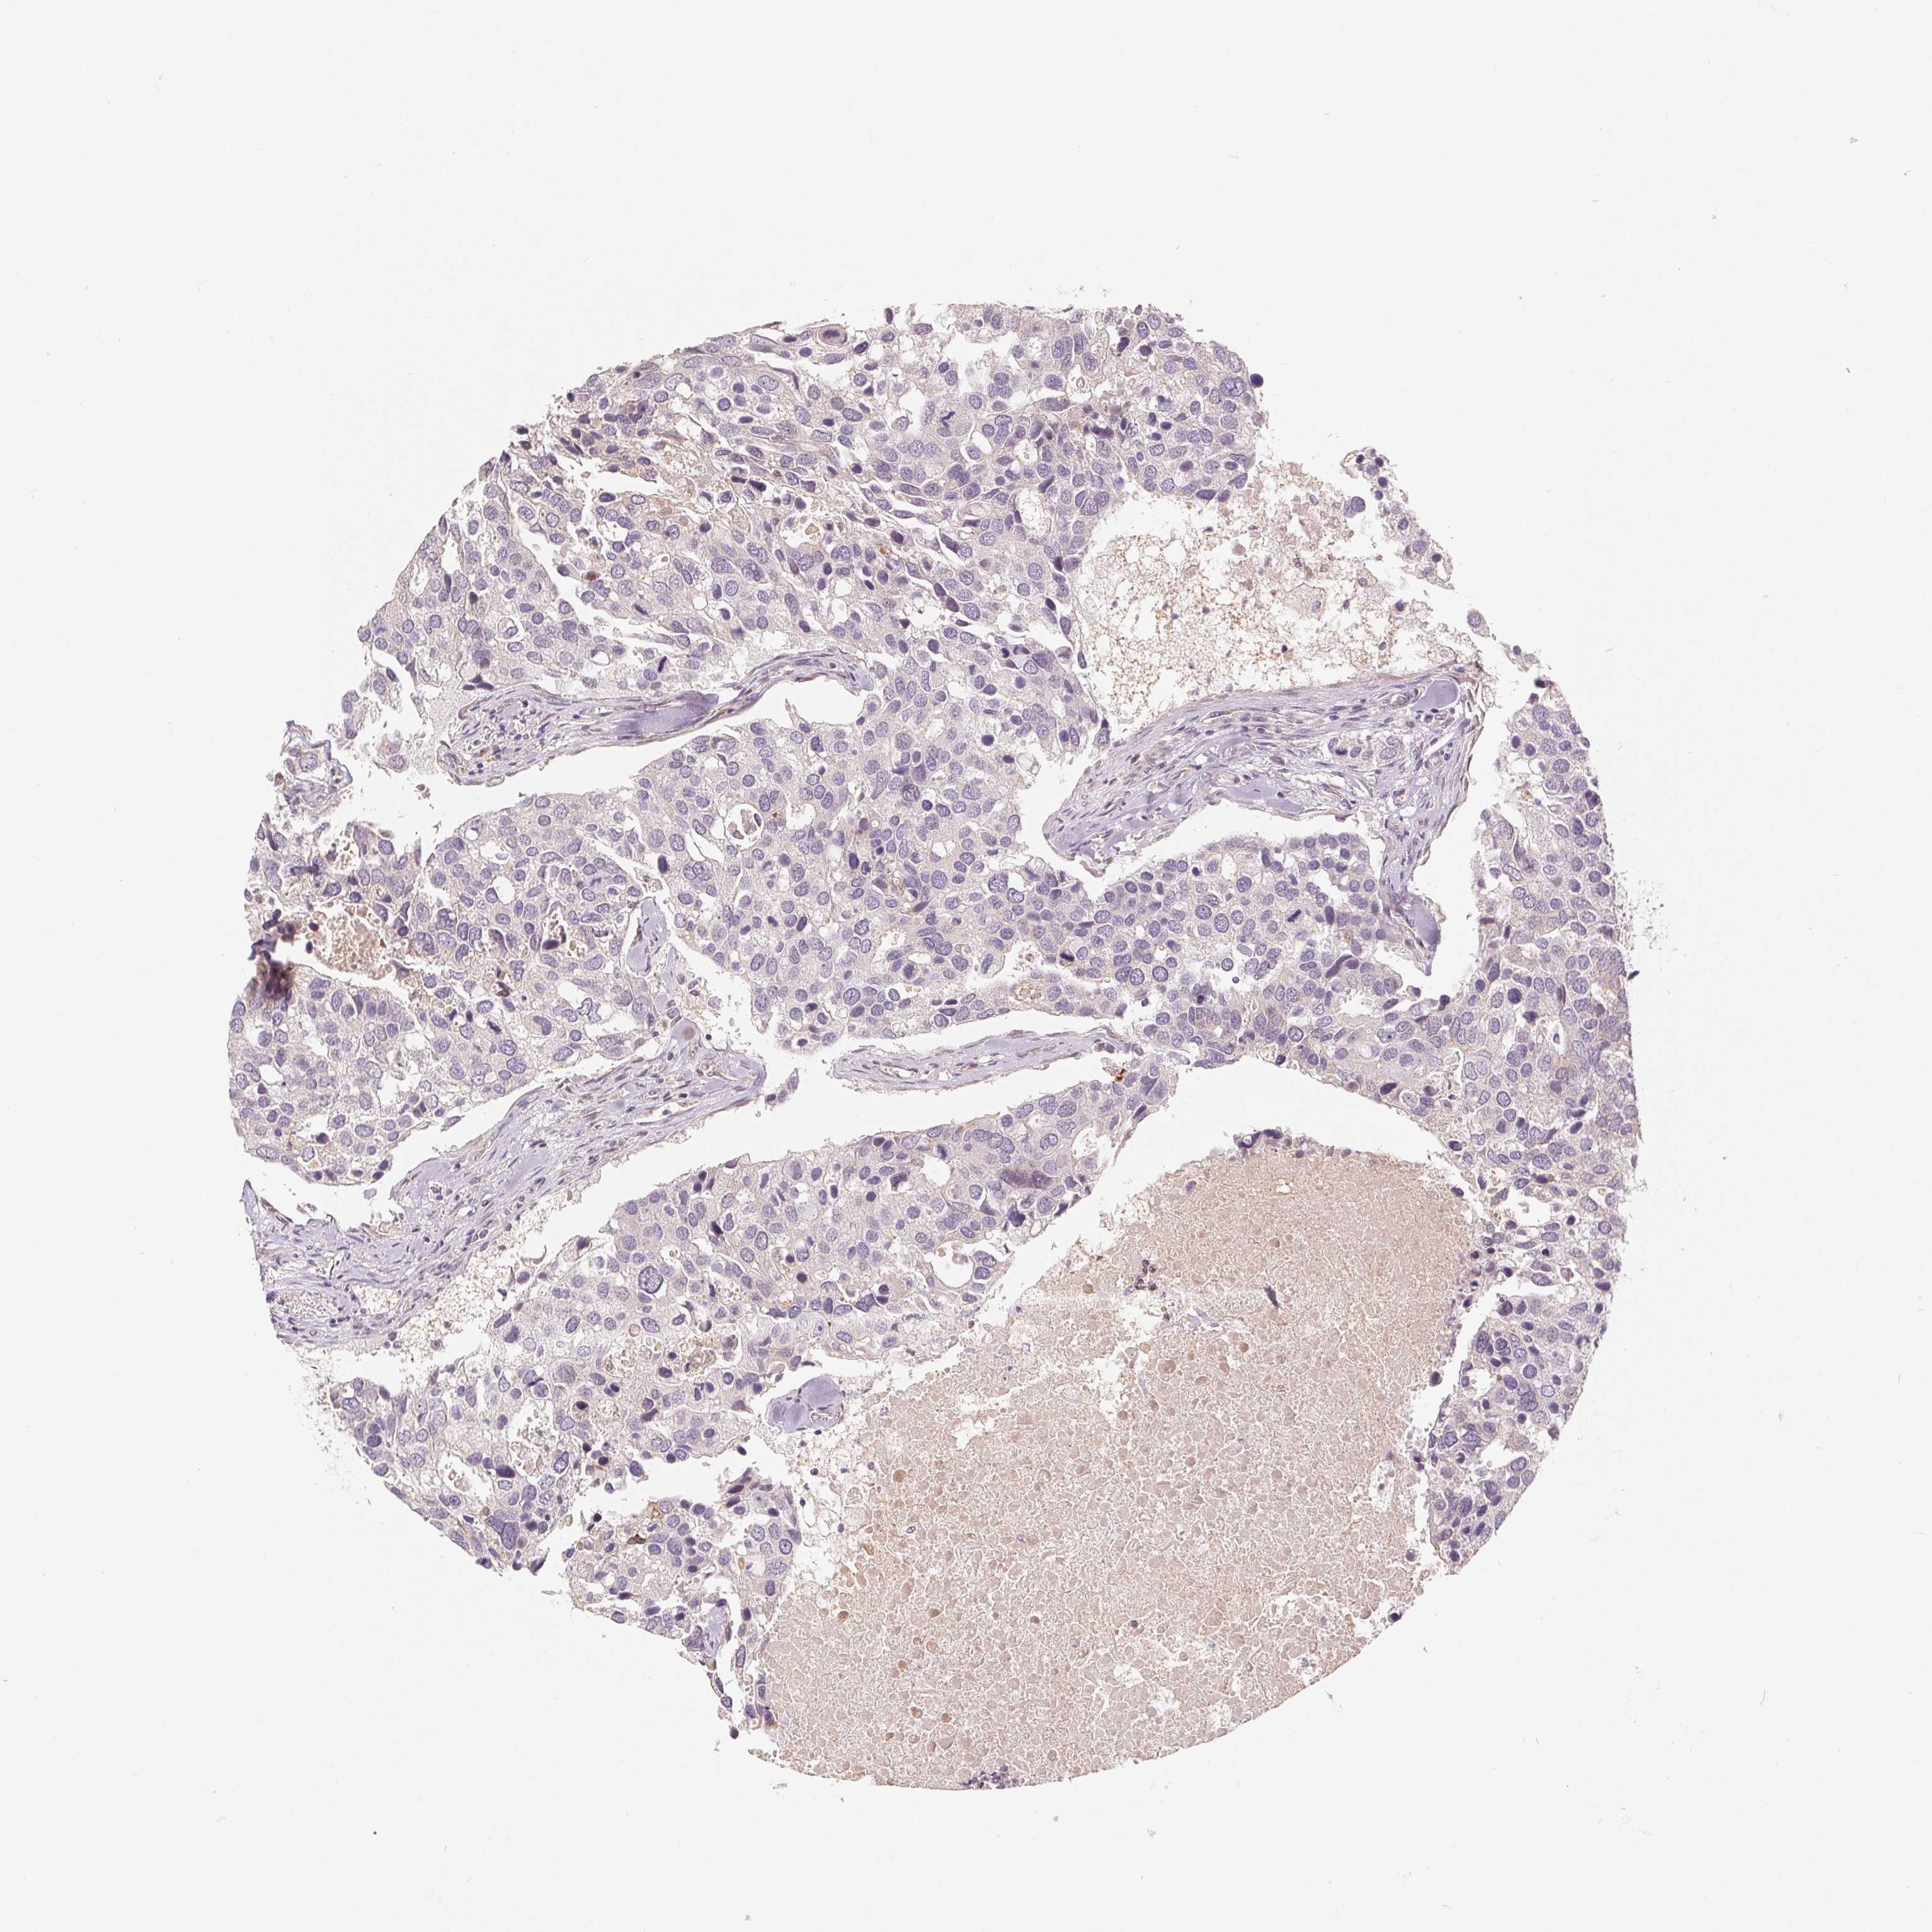

CANCER BREAST CANCER Show tissue menu

BRCA TCGA BRCA VALIDATION PROTEIN EXPRESSION